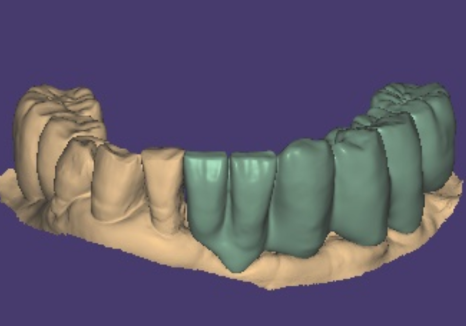

반면 디지털 가이드(네비게이션) 방식은

3D CT와 구강 스캐너 데이터를 결합해

컴퓨터상에서 미리 모의 수술을 해보는 방식이에요.

이를 통해 임플란트가 들어갈

최적의 경로를 찾고,

그 길을 그대로 안내해주는

서지컬 가이드라는 맞춤형 틀을 제작하게 됩니다.

구강스캐너로 본 뜬 스캔 데이터를 통해

컴퓨터로 정밀한 보철물을 설계합니다.

240514